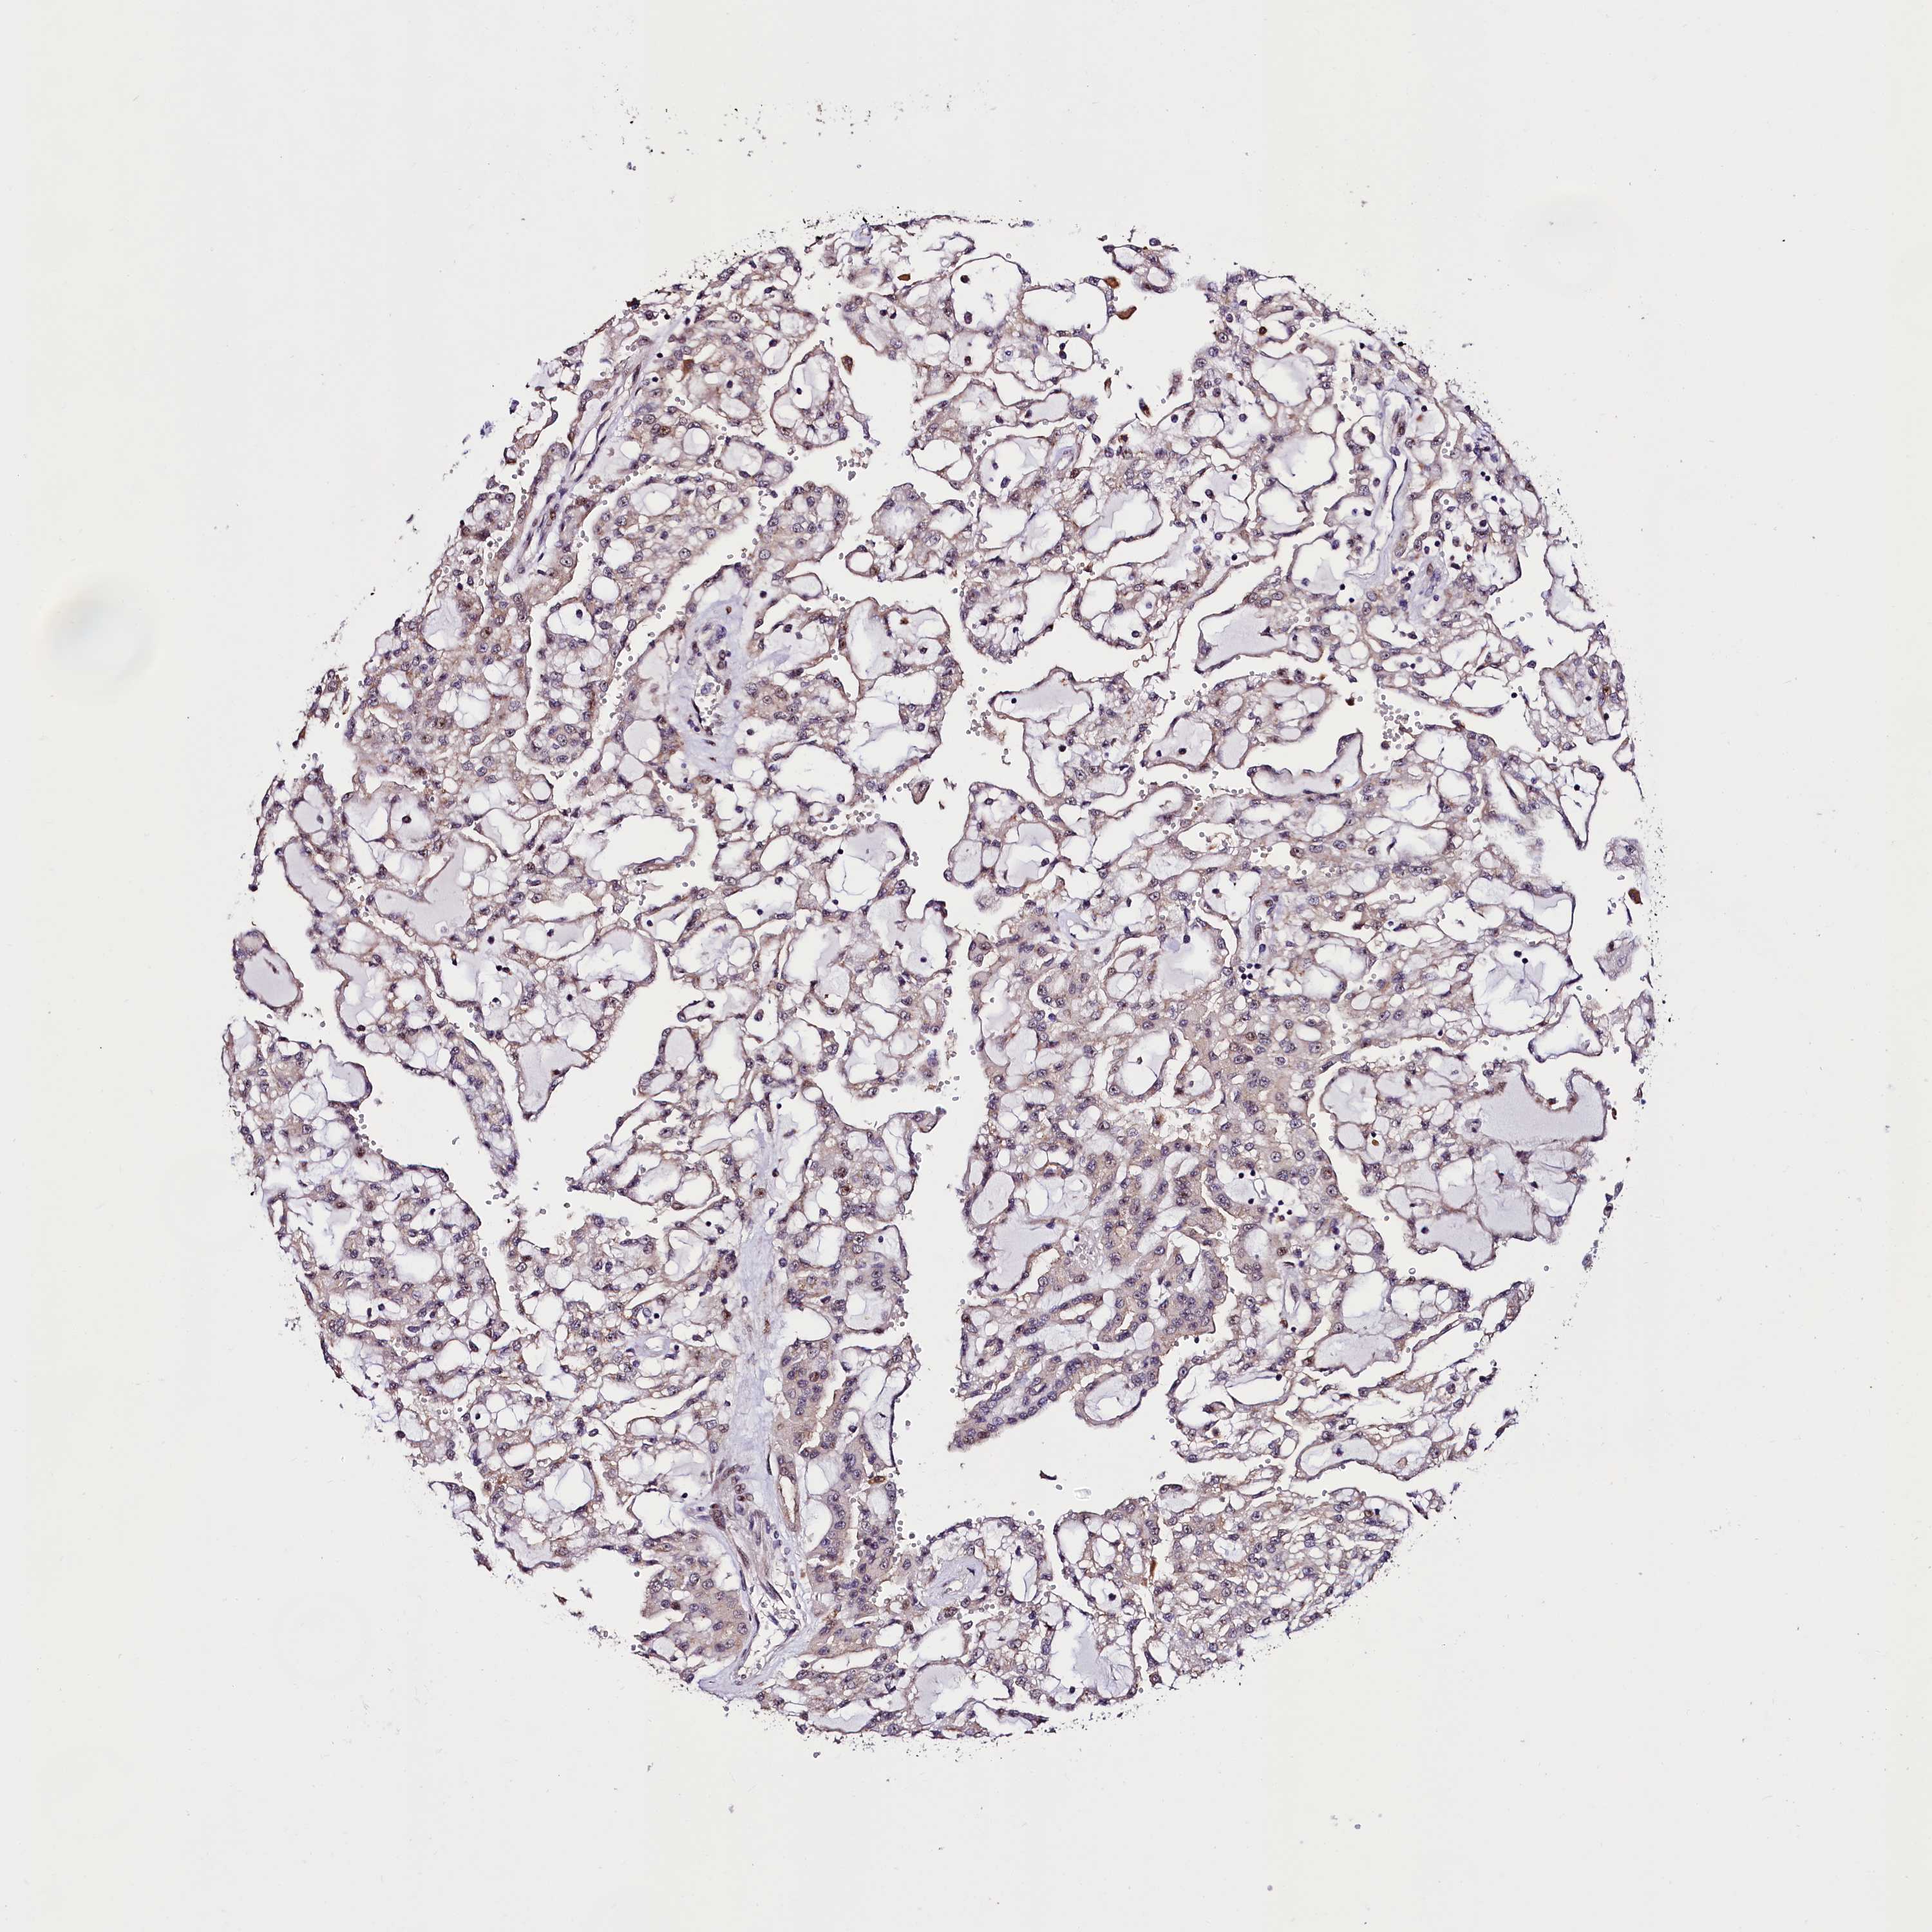

KIDNEY RENAL CLEAR CELL CARCINOMA (VALIDATION) - Interactive survival scatter ploti

The Survival Scatter plot shows the clinical status (i.e. dead or alive) for all individuals in the patient cohort, based on the same data that underlies the corresponding Kaplan-Meier plots. Patients that are alive at last time for follow-up are shown in blue and patients who have died during the study are shown in red.

The x-axis shows the expression levels (FPKM) of the investigated gene in the tumor tissue at the time of diagnosis. The y-axis shows the follow-up time after diagnosis (years). Both axes are complimented with kernel density curves demonstrating the data density over the axes. The top density plot shows the expression levels (FPKM) distribution among dead (red) and alive patients (blue). The right density plot shows the data density of the survived years of dead patients with high and low expression levels respectively, stratified using the cutoff indicated by the vertical dashed line through the Survival Scatter plot. This cutoff is automatically defined based on the FPKM cutoff that minimizes the p-score. The cutoff can be changed by dragging the vertical line or by entering a cutoff value in the square labeled "Current cut-off".

Under the Survival Scatter plot the p-score landscape (black curve; left axis) is shown together with dead median separation (red curve; right axis). Dead median separation is the difference in median mRNA expression between patients who have died with high and low expression, respectively. It is calculated as follows: median FPKM expression of dead patients with high expression - median FPKM expression of dead patients with low expression. This is intended to aid the user in visually exploring custom cutoffs and the associated p-scores and dead median separation.

Individual patient data is displayed and can be filtered by clicking on one or more of the category buttons on the top of the page. Categories describing expression level and patient information include: high, low, alive, dead, female, male and tumor stages. The scale of the x-axis can be toggled between linear and log-scale by clicking on the "x log" button. Mouse-over function shows TCGA ID, patient information and mRNA expression (FPKM) for each patient.

& Survival analysisi

Kaplan-Meier plots summarize results from analysis of correlation between mRNA expression level and patient survival. Patients were divided based on level of expression into one of the two groups "low" (under cut off) or "high" (over cut off). X-axis shows time for survival (years) and y-axis shows the probability of survival, where 1.0 corresponds to 100 percent.

TRMT112 is not prognostic in Kidney Renal Clear Cell Carcinoma (validation)

Best expression cut offi

Based on the FPKM value of each gene, patients were classified into two groups and association between prognosis (survival) and gene expression (FPKM) was examined. The best expression cut-off refers the FPKM value that yields maximal difference with regard to survival between the two groups at the lowest log-rank P-value. Best expression cut-off was selected based on survival analysis .

When clicking on this number, the vertical dashed line indicating cut-off, the interactive survival plot, and the Kaplan-Meier curve will be adjusted to show results based on the best expression cut-off.

: 280.95

Median expressioni

Median expression refers to the median FPKM value calculated based on the gene expression (FPKM) data from all patients in this dataset. When clicking on this number, the vertical dashed line indicating cut-off, the interactive survival plot, and the Kaplan-Meier curve will be adjusted to show results based on the median expression.

: N/A

Median follow up timei

Median follow up time refers to the median time (years) after diagnosis with this type of cancer, based on clinical data from all patients in this dataset.

P scorei

Log-rank P value for Kaplan-Meier plot showing results from analysis of correlation between mRNA expression level and patient survival.

N/A

5-year survival highi

5-year survival for patients with higher expression than the expression cutoff.

For melanoma and glioma, 3-year survival is shown.

5-year survival lowi

5-year survival for patients with lower expression than the expression cutoff.

TCGA RNA samplesi

RNA-seq data is reported as average FPKM (number Fragments Per Kilobase of exon per Million reads), generated by the The Cancer Genome Atlas (TCGA) .

Normal distribution across the dataset is visualized with box plots, shown as median and 25th and 75th percentiles. Points are displayed as outliers if they are above or below 1.5 times the interquartile range. FPKM values of the individual samples are presented next to the box plot.

Average pTPM 247.4

Number of samples 100